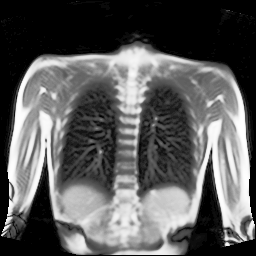

Refer to captionRefer to captionRefer to captionRefer to captionRefer to captionRefer to captionRefer to captionRefer to captionRefer to captionRefer to captionRefer to captionRefer to captionRefer to captionRefer to caption

Figure 5: Maximum inspiration (top row) and maximum expiration (bottom row) for different slice positions of one patient from back to front.

For a complete chest volume coverage, the lung is scanned at different slice positions as shown in Figure 5. At each slice position, a dynamic 2D+t image series with 140 images is acquired. For the further analysis of the image data, all images of one slice position need to be spatially aligned. We choose the image which is closest to the mean respiratory cycle as fixed image of the series. The other images of the series are then registered to this image. Our data set consists of 48 lung acquisitions of 42 different patients. Each lung scan contains between 7 and 14 slices. We used the data of 34 patients for the training set, 4 for the evaluation set, and 4 for the test set.